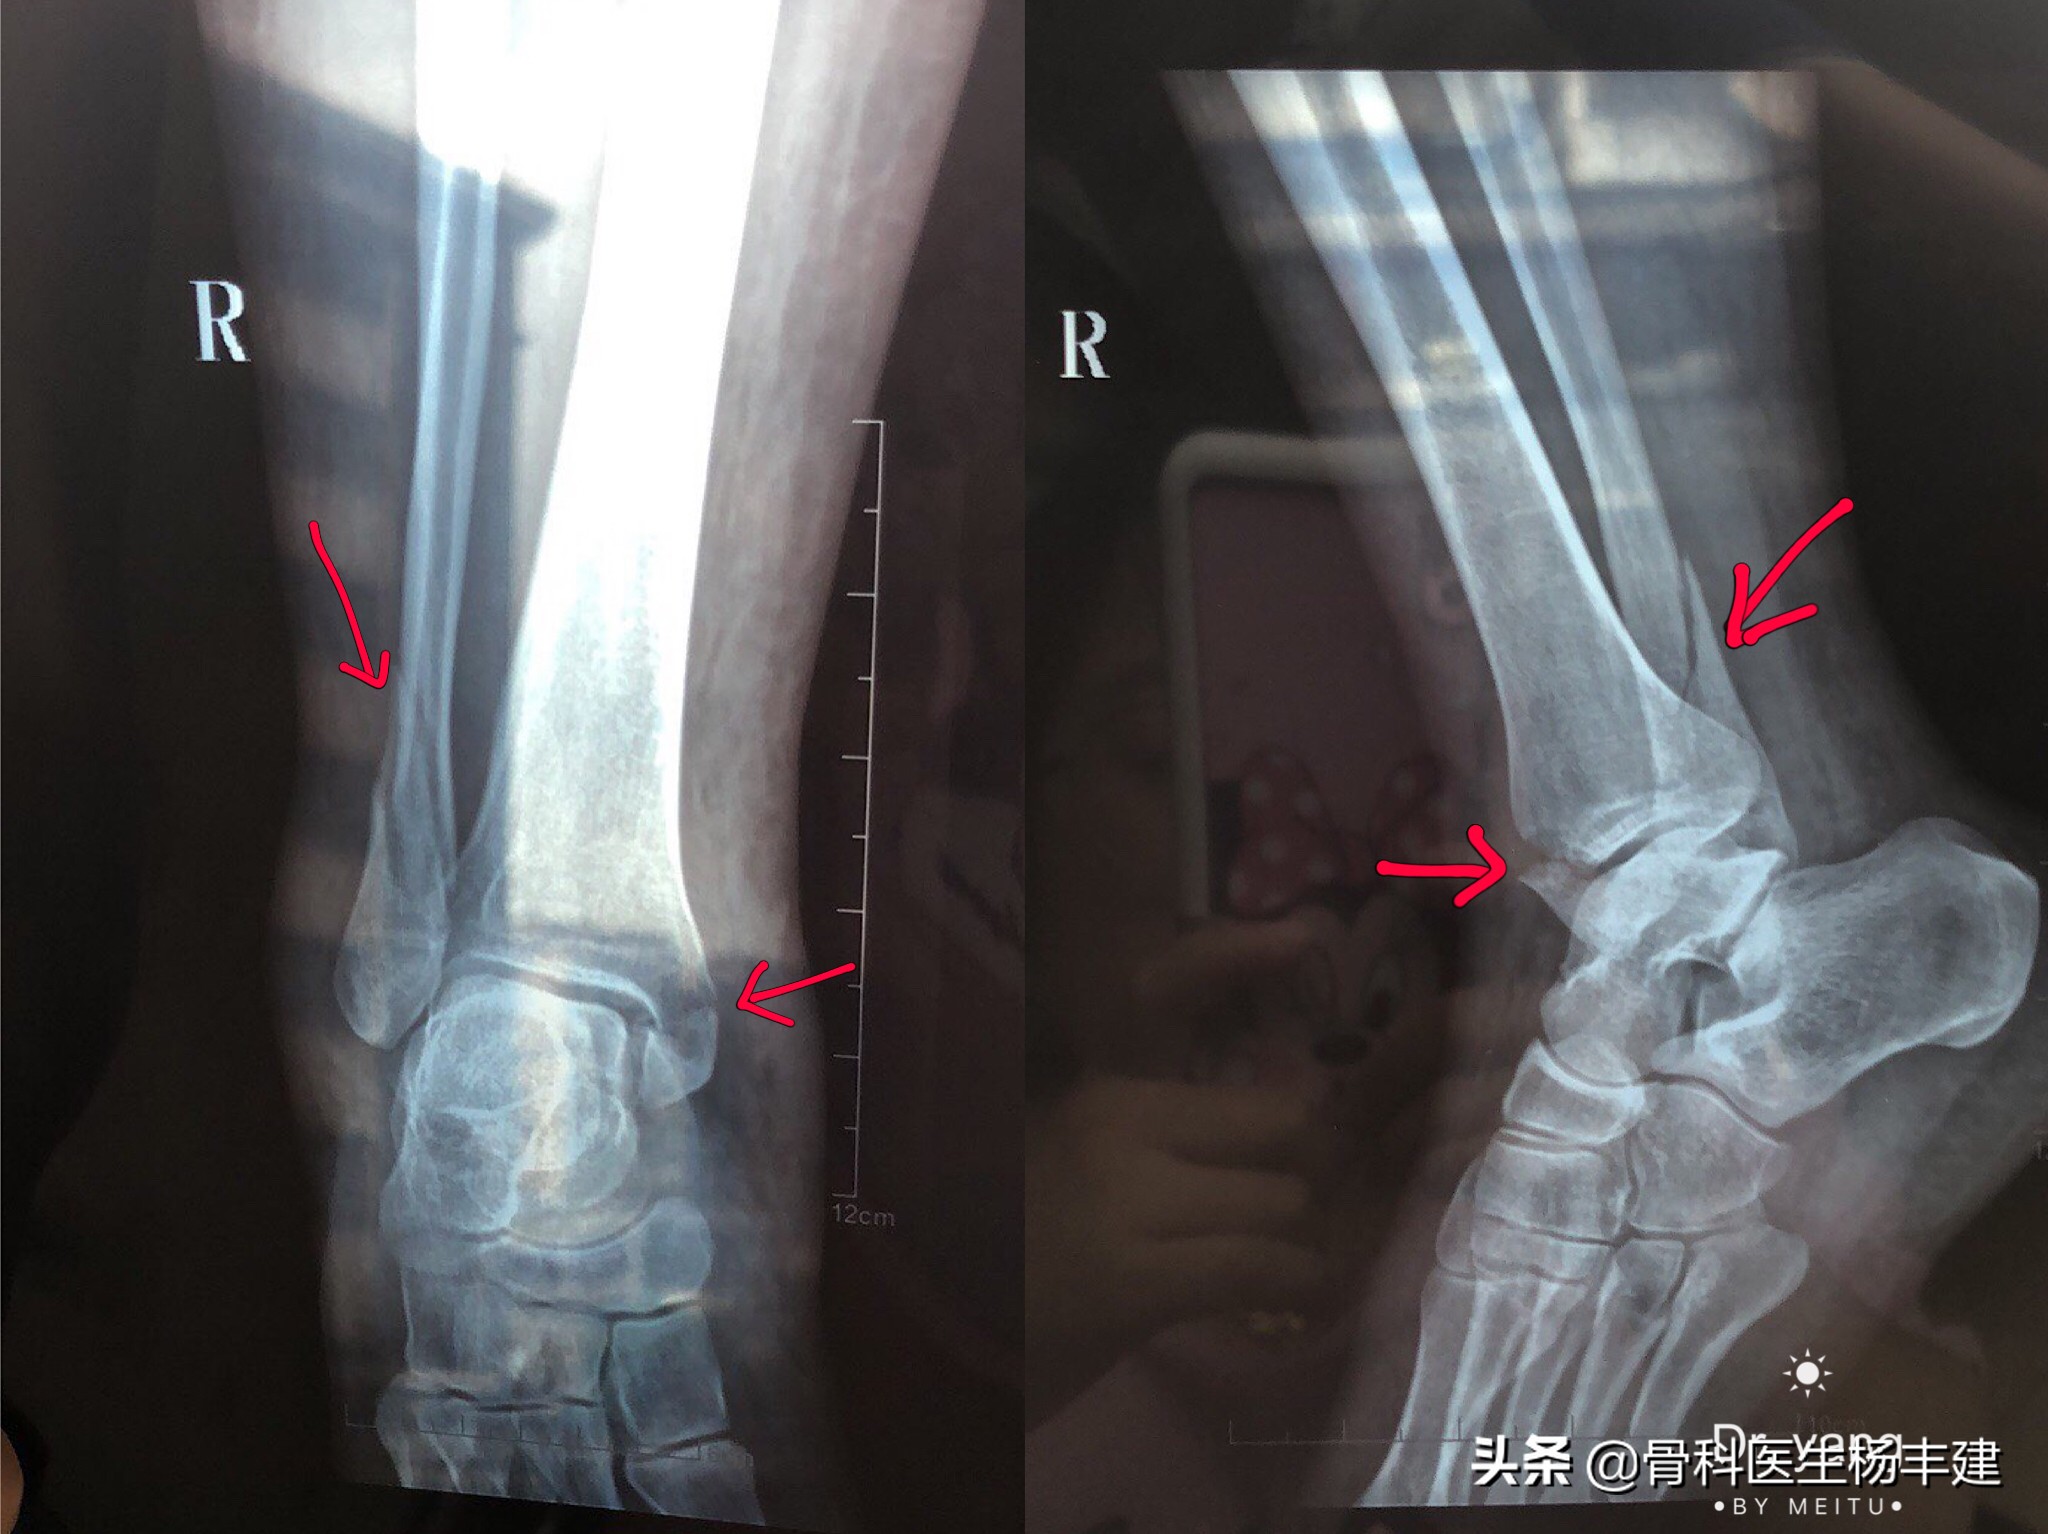

②骨折复位后,还需要关节下胫腓联合的宽度,以及踝穴两侧关节间隙的宽度。如果出现骨折完全复位,但是两侧关节间隙的宽度不对称,说明距骨的位置有问题,很可能存在下胫腓联合的脱位,也是需要修正的,通常使用螺丝钉收紧下胫腓联合。

手术前可见内侧踝穴明显增宽,距骨向外侧移位。手术中使用长螺钉收紧下胫腓联合,推挤距骨归位。